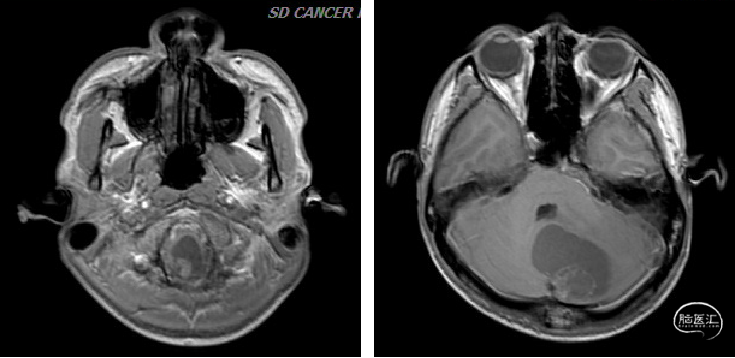

术前检查

术前CT

术前MRI

image.png

诊断及手术方式

术前诊断:

1.小脑、延髓占位(血管母细胞瘤)

2.梗阻性脑积水